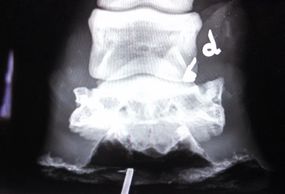

We have digital radiography to help us determine if there may be a fractured or injured tooth that may need to be fixed, or even extracted.

We offer digital radiography here at the clinic to aid in lameness diagnosis, we can take farrier views to aid your farrier in proper hoof care.